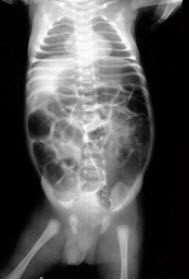

212、单项选择题

男,4月,出现腹胀半月,呕吐2天,出生后大便细少,如图所示,最可能的诊断为()

A.动力性肠梗阻

B.麻痹性肠梗阻

C.先天性巨结肠

D.绞窄性肠梗阻

E.肠套叠